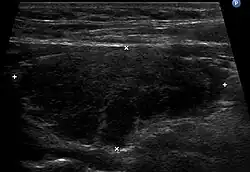

L'échographie de la thyroïde montre un goitre hypoéchogène[20],[18]. Le parenchyme thyroïdien devient plus hétérogène au cours de l'évolution. On peut notamment mettre en évidence des pseudo-nodules et des nodules de régénérations hyperéchogènes (white knight)[18]. Des ganglions récurrentiels peuvent être visualisés[18]. La vascularisation est hétérogène en Doppler couleur. L'étude en Doppler pulsé retrouve une élévation des vitesses systoliques[18], toutefois moindre que dans la maladie de Basedow.